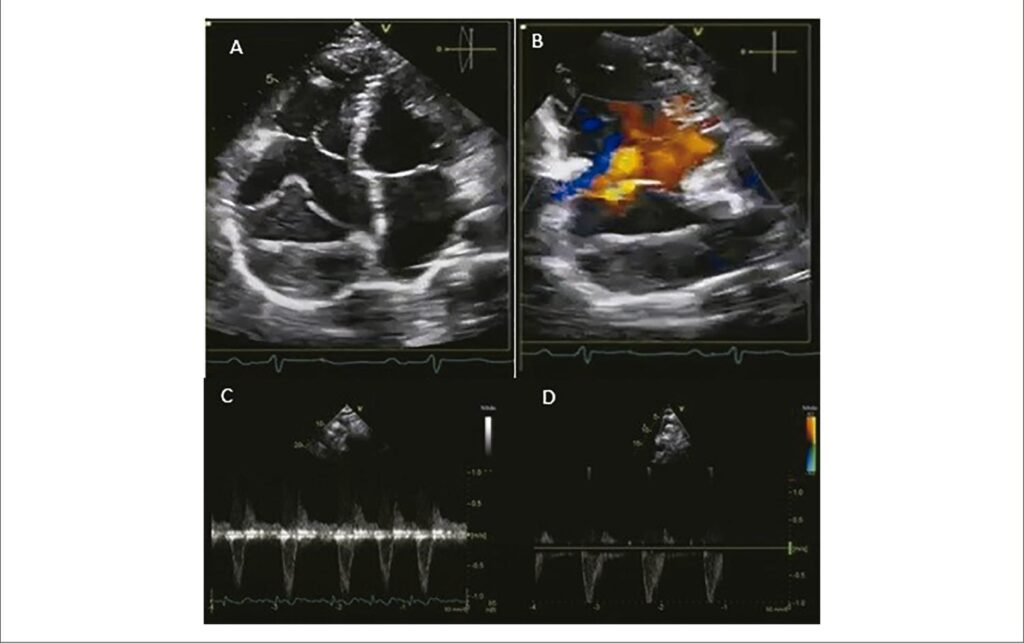

The authors report the case of a 29-year-old, female patient with palpitations, chest pain, and dyspnea on exertion. The patient was diagnosed with right coronary fistula and underwent percutaneous correction of the fistulous tract with an Amplatzer prosthesis.